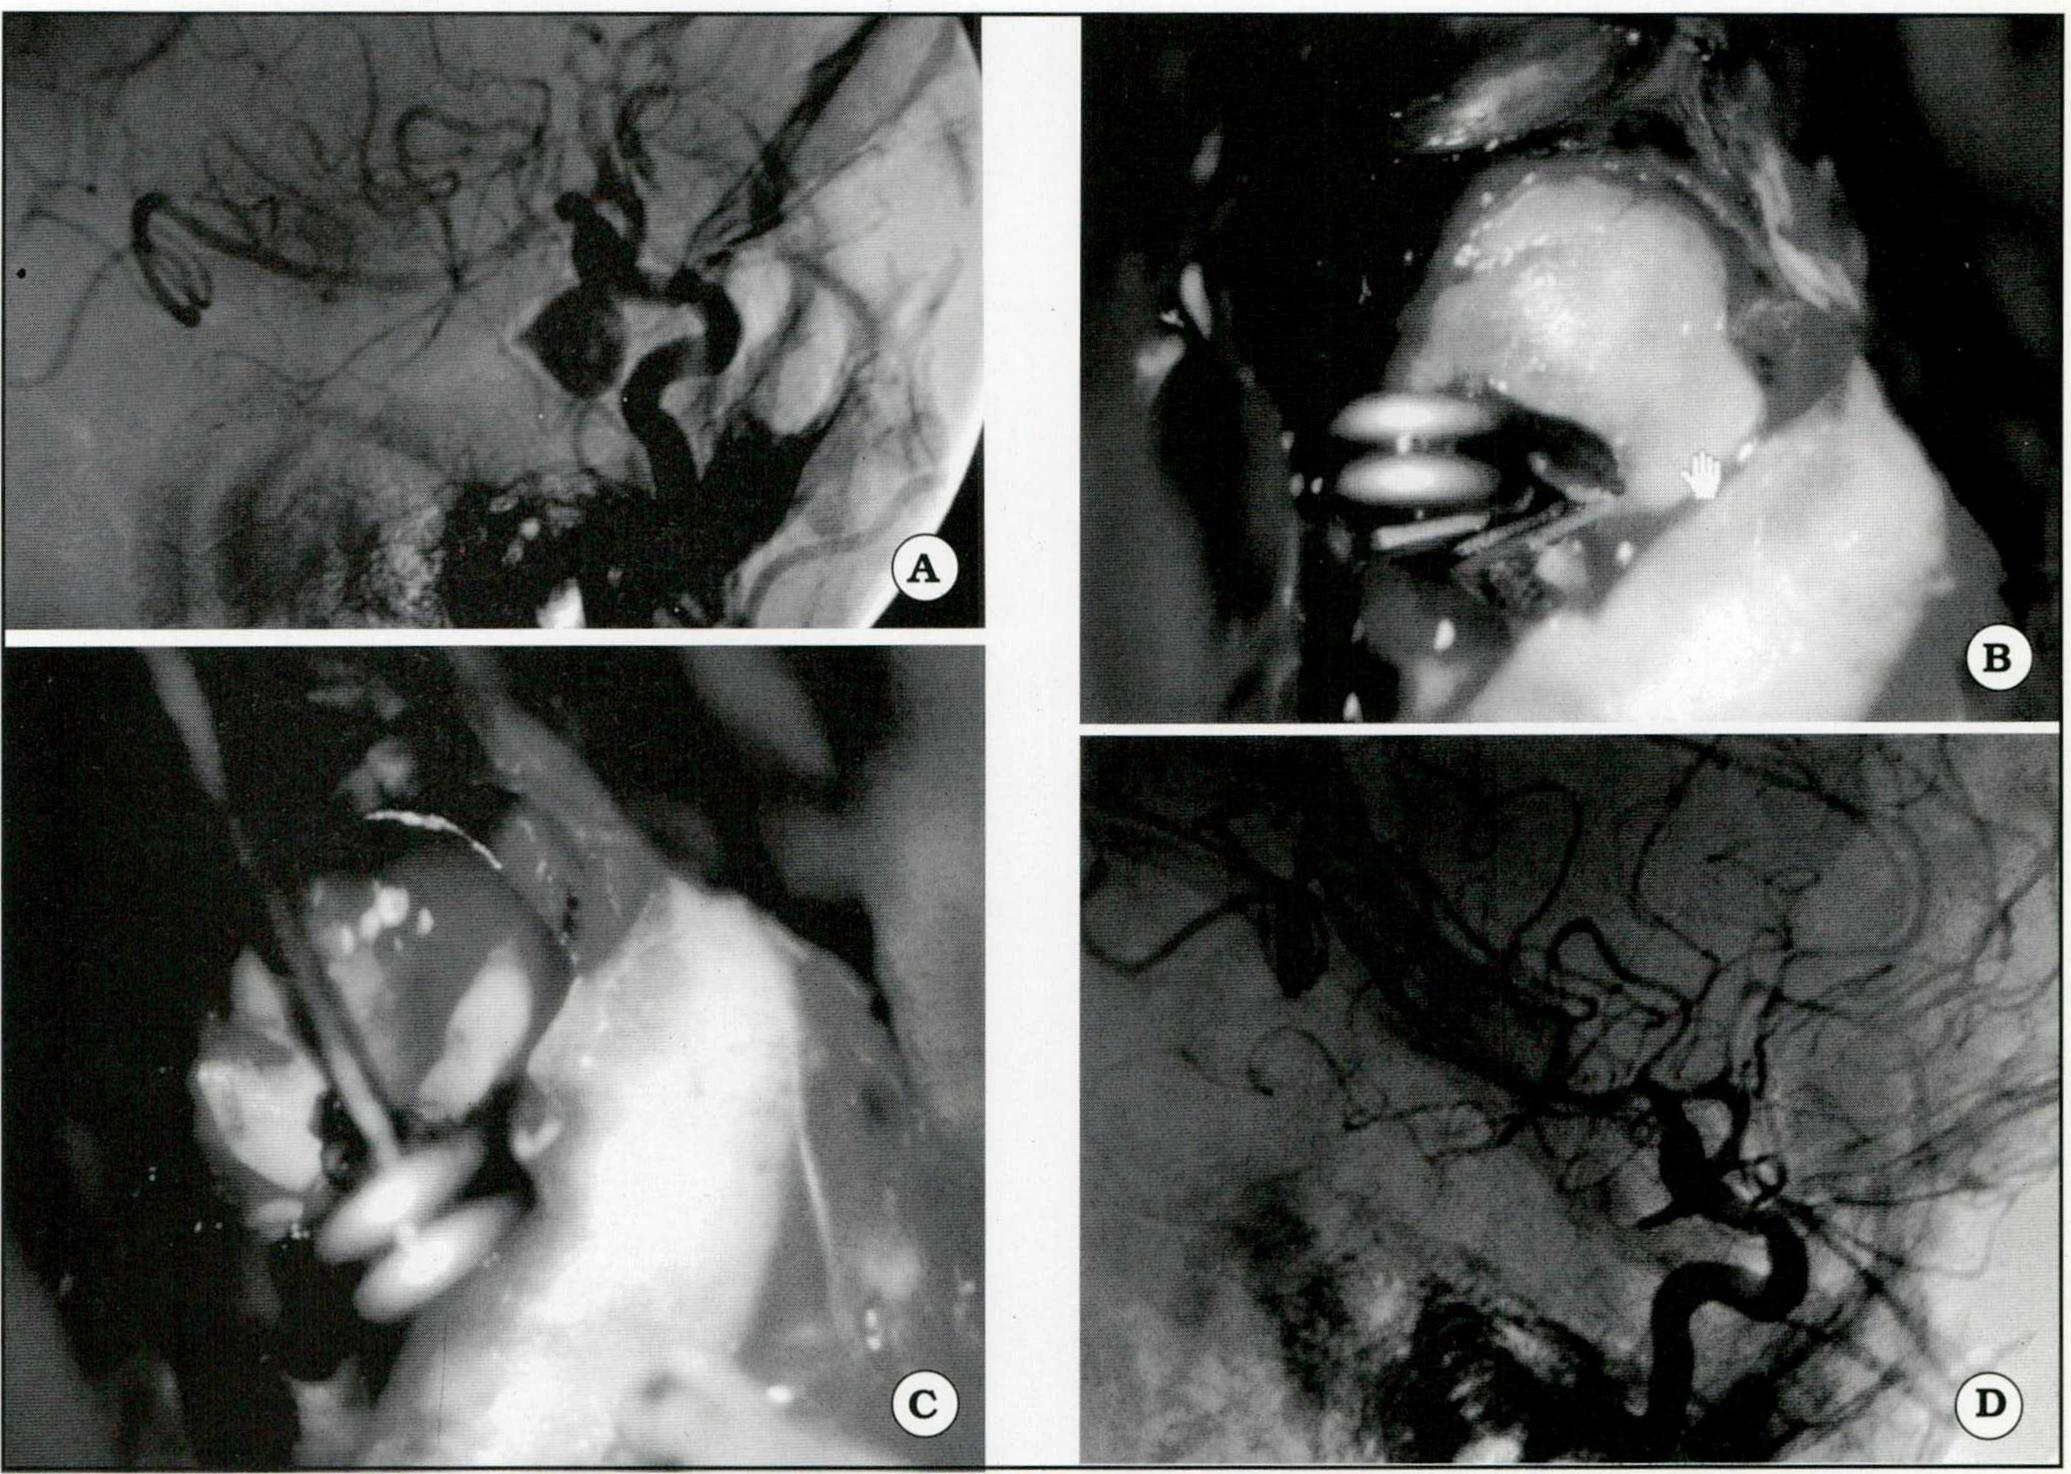

Se ejemplifican iconográficamente las siguientes situaciones:

Se realizó la punción del aneurisma en 29 casos (54,7%) y este procedimiento tendió a:

Fig. 1. A. Angiografía que muestra un aneurisma gigante del segmento comunicante posterior. B. Imagen intraoperatoria. Se observa el clipado del cuello aneurismá tico. C. Clipado del aneurisma. Se realizó punción del saco, maniobra cuyas ventajas se describen en el texto. D. Control angiográfico postoperatorio.